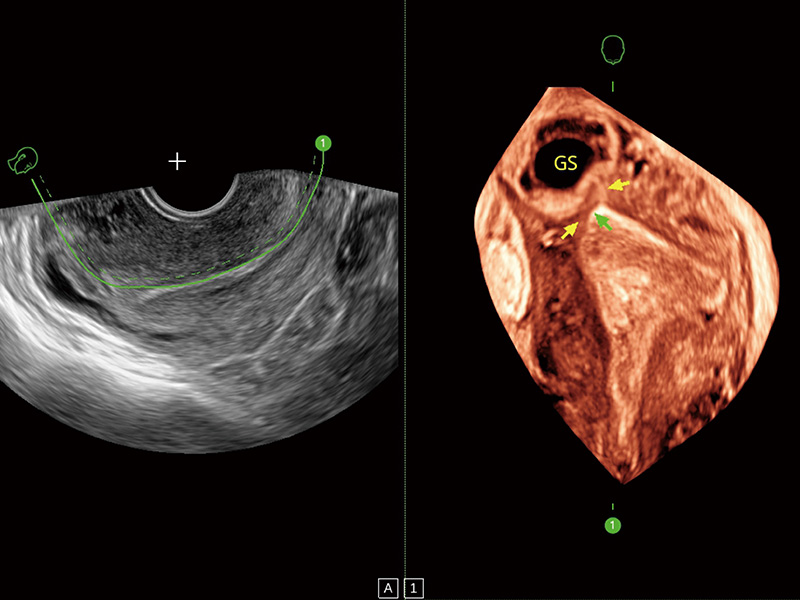

临床图

超声引导下双侧卵巢穿刺取卵